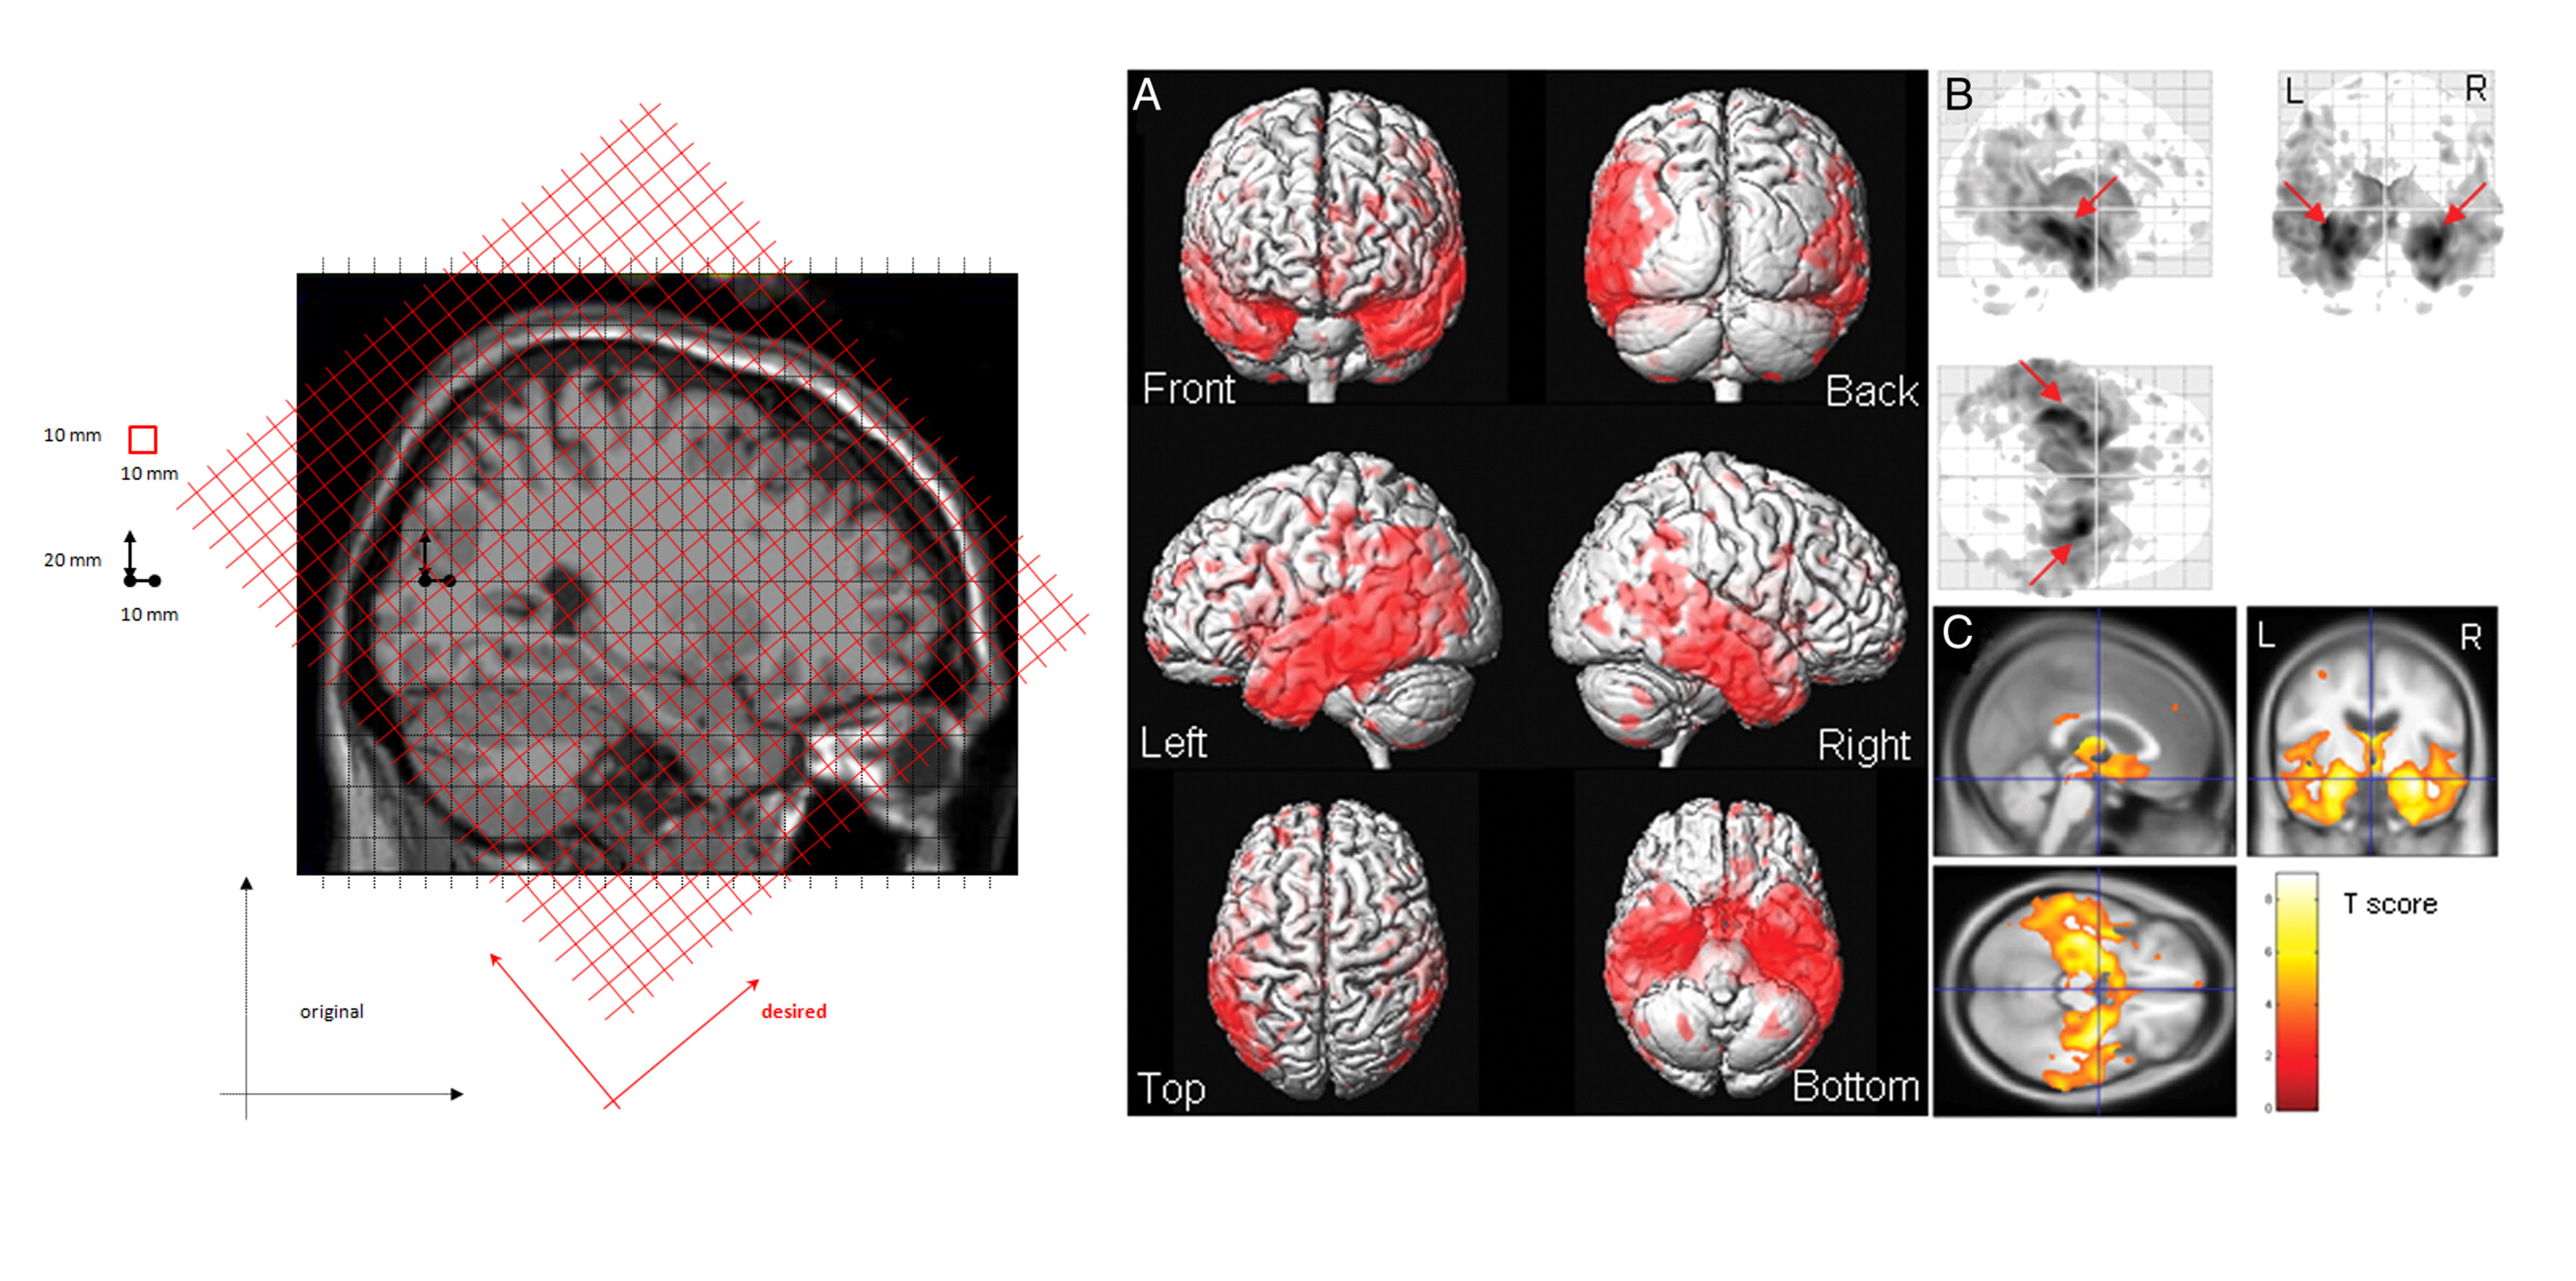

Volume (Voxel Based Morphometry [VBM])

Cortical Thickness

Shape (Morphology)

Structural Connectivity